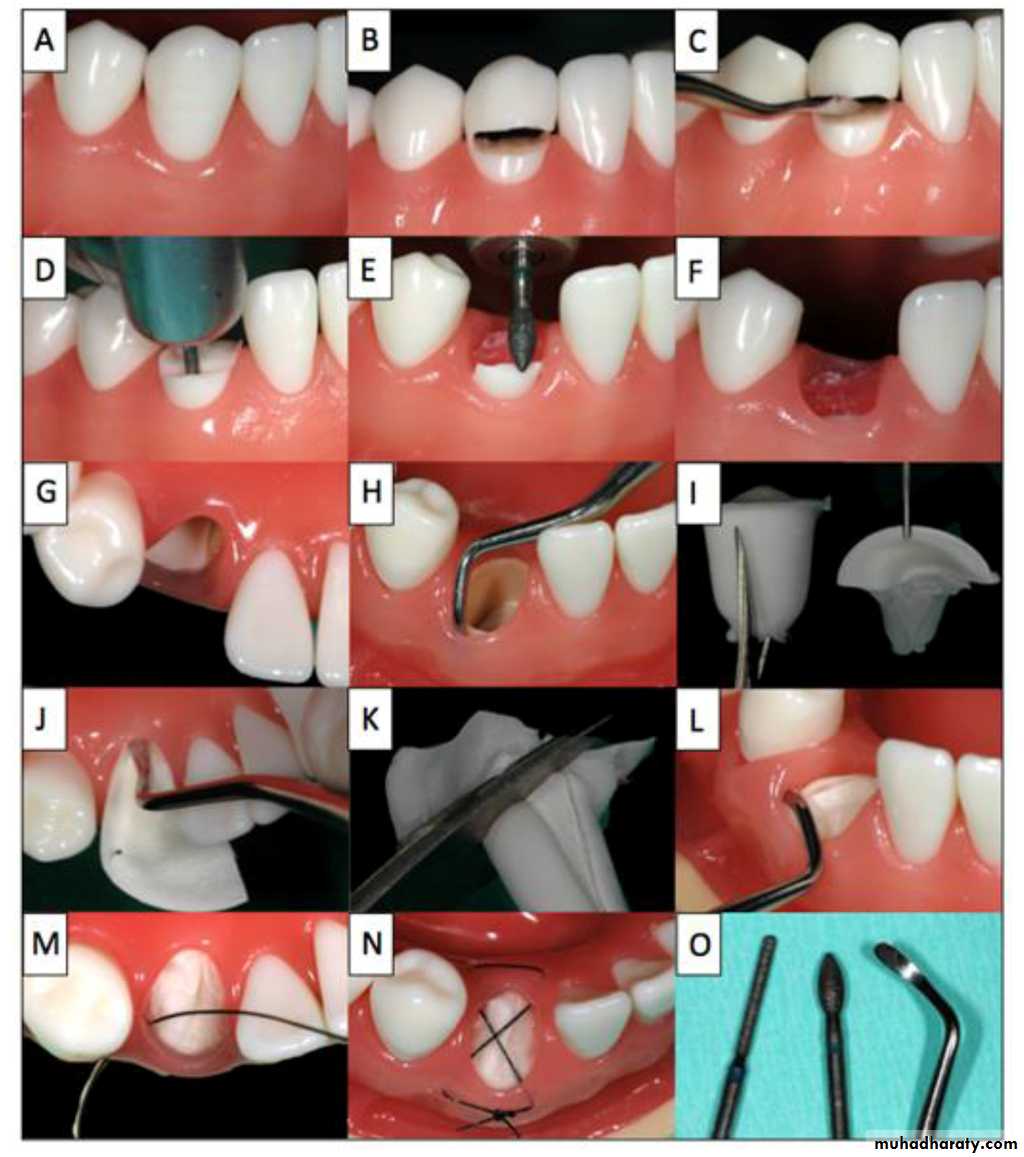

Frenectomy

Hypertrophic labial frenumAbnormal lingual frenum

high buccal frenum